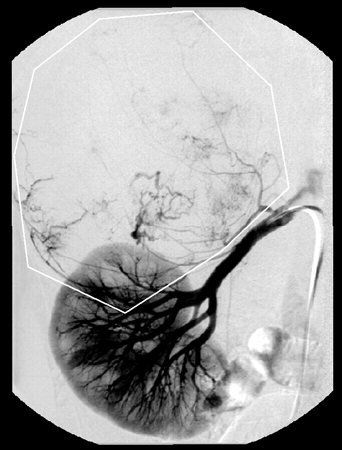

Наряду с преимуществами КТ имеет и ряд недостатков. При больших размерах опухоли трудно определить ее исходную локализацию, распространенность на другие органы и магистральные сосуды (Григорян С.В. и др., 1986). Основным методом, позволяющим ответить на данные вопросы, является АГ. Но, несмотря на тридцатилетний опыт применения АГ при опухолях надпочечников, до настоящего времени не установлено специфических ангиографических признаков, присущих какой-либо определенной гистологической форме опухоли. Тем не менее ангиографическая картина в большинстве случаев достаточно характерна, чтобы установить исходную локализацию опухоли, степень ее васкуляризации, источники кровоснабжения и распространение на окружающие органы и ткани (рис. 3, 4).

Рисунок 3. Селективная артериография (артериальная фаза) — умеренно васкуляризированная опухоль (феохромоцитома) правого надпочечника

Рисунок 4. Ангиография (паренхиматозная фаза) — умеренно васкуляризированная опухоль (феохромоцитома) правого надпочечника